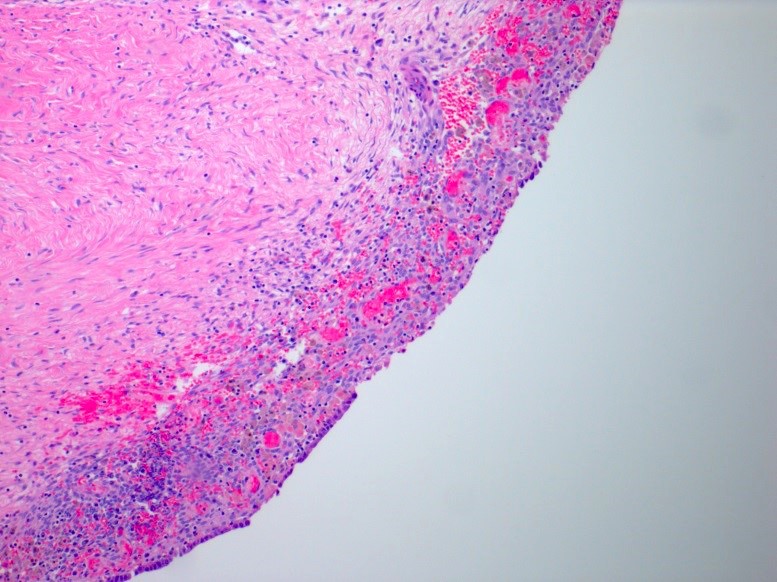

Gross description

- Ovarian endometriotic cysts (endometriomas) have fibrotic walls, a smooth lining and dark brown cyst contents (chocolate cyst), often adherent to adjacent organs

Microscopic (histologic) description

- Endometrial type stroma

- Often contains fine capillary network

- Evidence of chronic hemorrhage (hemosiderin laden or foamy macrophages)

- Necrotic pseudoxanthomatous nodules: central necrosis surrounded by histiocytes and outer fibrous zone

Microscopic (histologic) images